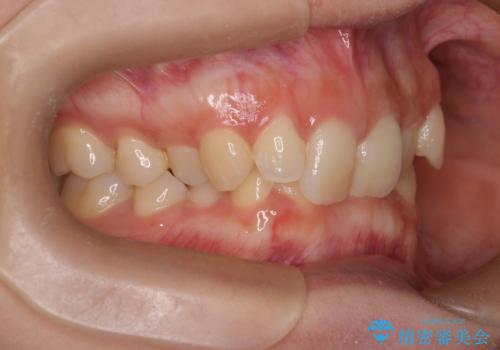

ディープバイト改善のためのインビザライン治療

- 患者様は、全体的な歯列のガタガタとディープバイト(深い噛み合わせ)を主訴として来院されました。診断の結果、ディープバイトを改善するためには、歯列全体の拡大が必要であると判断しました。治療には、透明なマウスピース型矯正装置「インビザライン」を使用し、歯を適切に拡大しながら歯並びを整える計画を立てました。治療期間はおおよそ2年を見込んで進め、最終的に見た目にも大きく変化をもたらすことを目指しました。

ディープバイトの治療には、奥歯の高さや前歯の位置に対する繊細な調整が必要です。本症例では、インビザラインによる歯列拡大を行うことで、噛み合わせを改善し、歯並び全体を整えました。治療過程では、歯間のスペースを確保するため、IPR(インタープロキシマルリダクション)を適宜行い、無理なく歯列の調整を行いました。治療後は、歯並びが大きく改善され、患者様の見た目にも大きな変化が現れました。インビザラインは透明で目立たず、治療中の見た目を気にされる患者様にも配慮した治療法です。